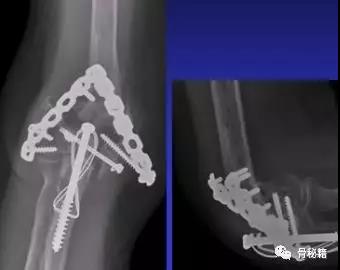

适当的固定技术原则

1、最大限度地固定远端碎片2、确保远端节段的所有固定有助于提高髁间水平的稳定性3、不建议使用三分之一管型板,因为它们太弱的并易于断裂,尤其是在粉碎干骺端

4、钢板长度也很重要:板应在近端以不同水平,以避免在肱骨干骨中形成应力集中

5、解剖锁定钢板板通过卓越的生物力学特性提供更好的临床疗效

6、良好的固定需要两个板,平行or垂直?在肱骨远端骨折中,一块钢板通常不足以保证良好的稳定性,而在其他骨折(例如,胫骨近端和股骨远端)中,LCP的引入消除了对双柱固定的需要。应谨慎使用单侧钢板板,仅在单柱损伤的情况下可以应用。

7、钢板如何搭配?迄今为止,通常使用前两种钢板的固定。AO推荐在治疗中应用垂直钢板。然而,这种方法受到了广泛的批评 - 主要是因为通过后外侧板难以获得足够的螺钉数量和前后方向的长度的螺钉固定。与垂直钢板相比,平行板配置似乎提供了更好的生物力学性能。实在不行的时候再用三钢板技术

固定的八个细节:1、每个螺钉都应该经过钢板固定2、每个螺钉固定骨折块的螺钉,在他的对侧应该也有一个钢板的把持3、在远端一定要打满螺钉4、每个螺钉要尽可能的长5、每个螺钉需要尽量的对关节面的骨块进行固定6、螺钉应通过交叉锁定在一起,从而形成角稳定结构并将内外侧柱连接在一起7、钢板需要再髁间完成加压8、所使用的板必须足够坚固并且足够坚硬以抵抗在髁上水平处的断裂或弯曲。